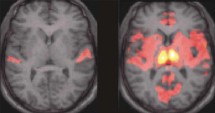

Momento tónico y fásico del cerebro en el sueño. Max-Planck-Institut für Psychiatrie

Lo han conseguido registrando la actividad cerebral de voluntarios mientras dormían, a través de imágenes de resonancia magnética funcional o RMF, que permiten mostrar las regiones cerebrales mientras ejecutan una tarea determinada.

Cuando los movimientos oculares son especialmente rápidos, la actividad en algunas partes del cerebro es muy intensa. Entonces, los ruidos que oímos en ese momento (en el caso del experimento ruidos repetitivos o la melodía de un piano) son completamente ocultados por el cerebro. Esta “subfase” REM ha sido denominada “fásica” y se ha descubierto que no es continua, sino que va a “saltos”.

Entre dos subfases fásicas, el durmiente pasa por otra subfase muy breve, bautizada como “tónica”, en la que los estímulos sensoriales sí son registrados por el cerebro y los movimientos oculares rápidos no aparecen.